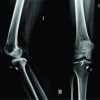

The patient was a 40-year-old man (height, 178 cm; weight, 74 kg; and handedness, right-handed). He had no history of diseases that could cause bone fragility or any history of malignant tumors. He played baseball only a few times a year for recreational purposes. He had a gradual onset of pain in his left hip joint after throwing a ball as a baseball pitcher. When he consulted a neighborhood doctor, X-ray images (Fig. 1) did not show any obvious anomalies. However, the pain persisted even after a month. Therefore, he was referred to our department. The range of passive motion of the hip joint was as follows: right flexion, 120°; left flexion, 100°; right abduction, 30°; left abduction, 30°; right adduction, 15°; left adduction, 15°; right internal rotation, 10°; left internal rotation, 10°; right external rotation, 40°; and left external rotation, 40°. He experienced pain during deep flexion of the left hip joint. However, the results of Patrick test and FADIR test were both negative. In addition, X-ray images (Fig. 2) did not show obvious anomalies.